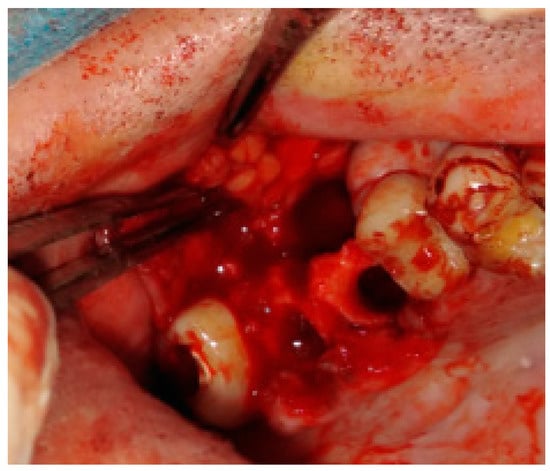

Figure 6. Bichat fat pad mobilization to cover the bone defect and close the oro-antral communication.

Figure 7. The surgical specimen consisted of granulation tissue, bone with inflammatory changes, and sinus retention cyst.

Figure 3. The bone defect was covered with the Bichat fat pad after mobilization. The entire defect will be sutured with vertical mattress sutures to the palate to ensure its proper position.